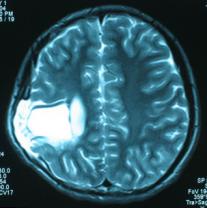

头颅CT和MRI可见颅骨缺损区下方软脑膜囊肿、脑软化灶或脑室穿通畸形(图2)。

图2:①和②CT及骨窗相显示右顶部颅骨缺损,其下方脑组织呈低密度改变;③-⑥MRI右顶局部颅骨缺如,脑组织轻度向外膨隆,右顶叶侧脑室体部旁局部脑组织缺如,代之以囊性长T1、长T2信号。